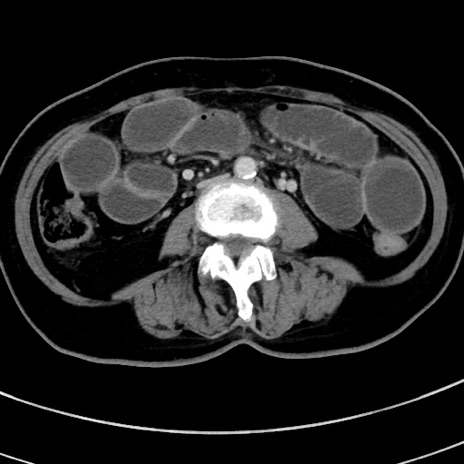

症例9(横断像)

【症例】 60歳代女性

【主訴】むかつき、みぞおちの痛み

【現病歴】3日前よりむかつきがあり、食事がとれない。

【既往歴】糖尿病

【身体所見】発熱なし、心窩部圧痛軽度あるも、腹膜刺激症状なし。

【データ】WBC 7400、CRP 1.92